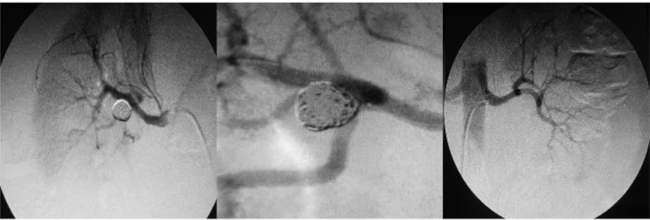

Con sospecha de hipertensión arterial secundaria, probablemente renovascular se realiza Rx. de abdomen y ecografía abdominal que resultaron normales. Por su parte, en la ecografía renal se observa una imagen anecoica en la pelvis renal derecha de 1,95 cm por 1,44 cm. El eco-Doppler de arterias renales presentó una velocidad flujo pico sistólico (VFPS) de la arteria renal derecha (ARD) principal de 210 cm/s (VN <180 cm/s), un índice de resistencia (IR) mayor de 0,7 (VN <0,70), tiempo de aceleración de 0,13 cm/s (VN <0,1). La arteria renal izquierda (ARI) principal tiene una VFPS de 173 cm/s y un IR igual a 0,65. Se realiza una angiografía por sustracción digital renal en la que se observa una lesión grave en el tercio medio de la ARI y otra lesión grave en el tercio medio y pos de la ARD; se objetiva un aneurisma sacular de cuello estrecho en la bifurcación de la AR principal derecha. Tras valorar las opciones terapéuticas, se optó por realizar un tratamiento endovascular que consiste en la exclusión endovascular del aneurisma y la embolización con 5 espirales (coils) (Barricade): 1 de 9 × 30, 2 de 8 × 27 y 2 de 7 × 19 mm, con lo que queda compactado el aneurisma. A continuación, se realiza una angioplastia de AR principal derecha con colocación de stent de 4,30 mm × 16 mm. Al mes siguiente, se practica una angioplastia con colocación de stent Corflex de 4,0 mm × 16 mm a la AR principal izquierda.

La evolución de la paciente fue satisfactoria luego de la intervención: Eco-Doppler color de arterias renales: ARD: VFPS: 170 cm/s, (IR) 0,63; ARI: VFPS: 165 cm/s, (IR) 0,60 y MAPA: HTA sistólica diurna/nocturna, grado I non dipper. Al año, una angiografía selectiva renal fue normal. La paciente continúa normotensa y en tratamiento con carvedilol, amlodipina, aspirina, estatinas y suspende clopidogrel.